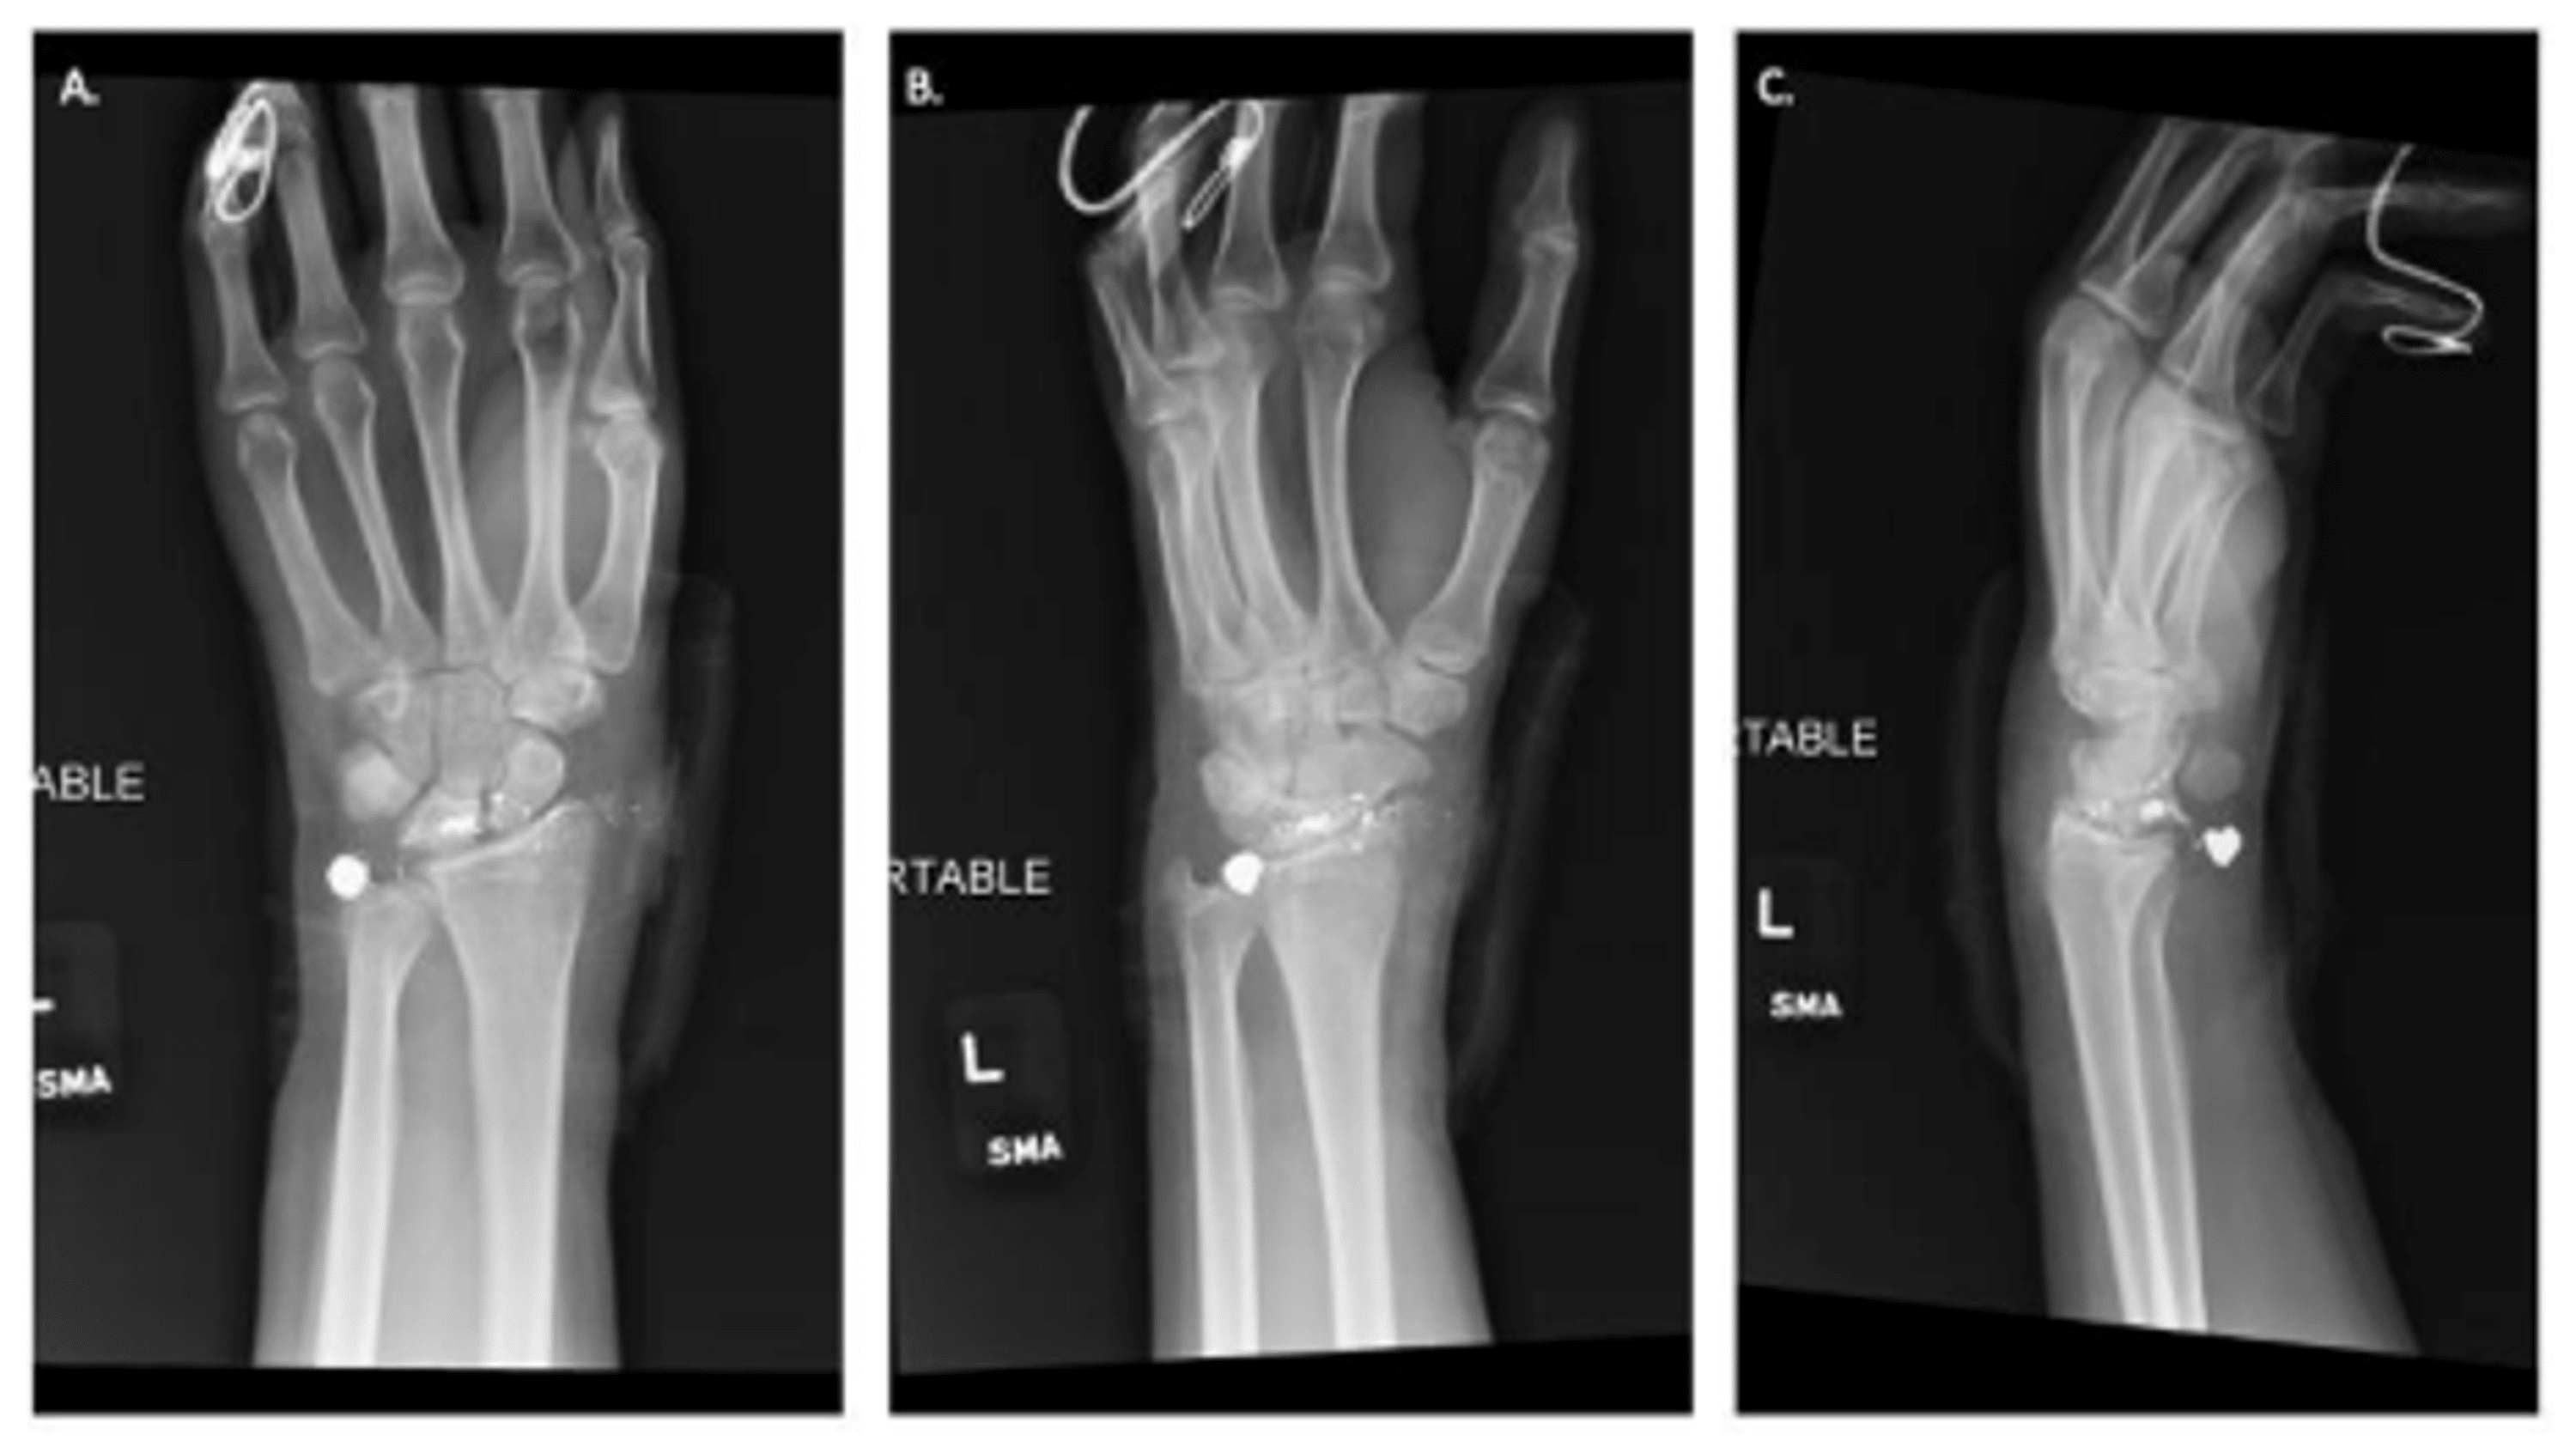

From www.cureus.com

Outpatient Treatment Guidelines of Gunshot Wound to the Hand and Wrist Medical Term For Bullet Wound — gsw stands for gunshot wound, a type of penetrating abdominal injury that can cause serious complications. Call 911, and follow these steps to stop bleeding and help a gunshot victim. Find out how bullets can fracture. — learn about the epidemiology, etiology, pathoanatomy, presentation, imaging, and treatment of gun shot wounds. — indicators of possible clothing. Medical Term For Bullet Wound.